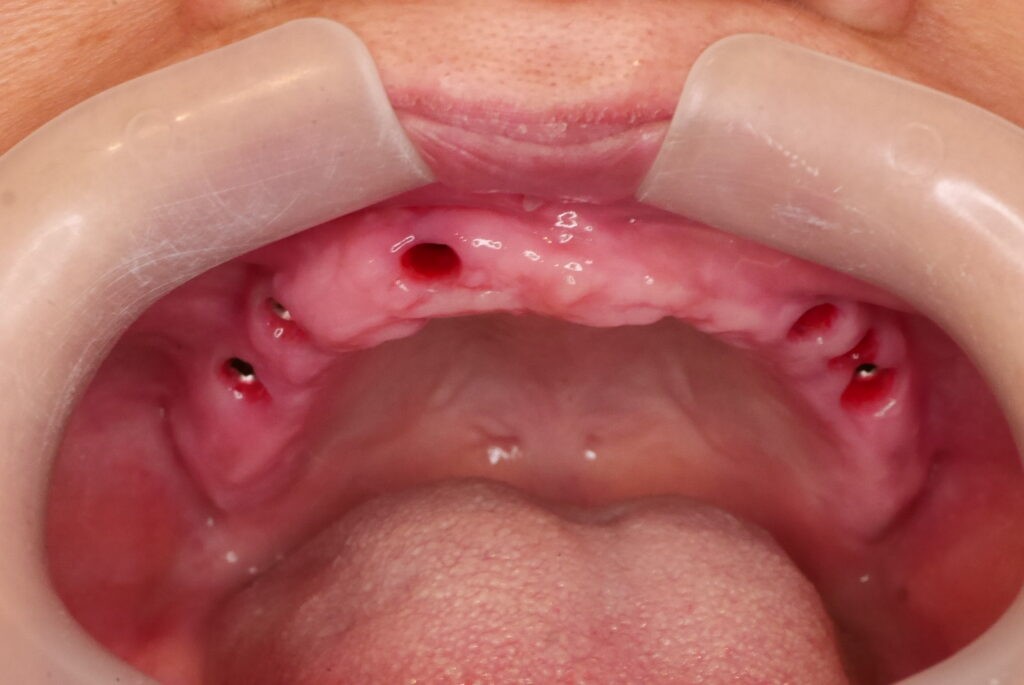

數位取模,置入植體掃描桿

數位取模 德國口掃機 口內精準掃描

數位取模 電腦設計 電腦製作